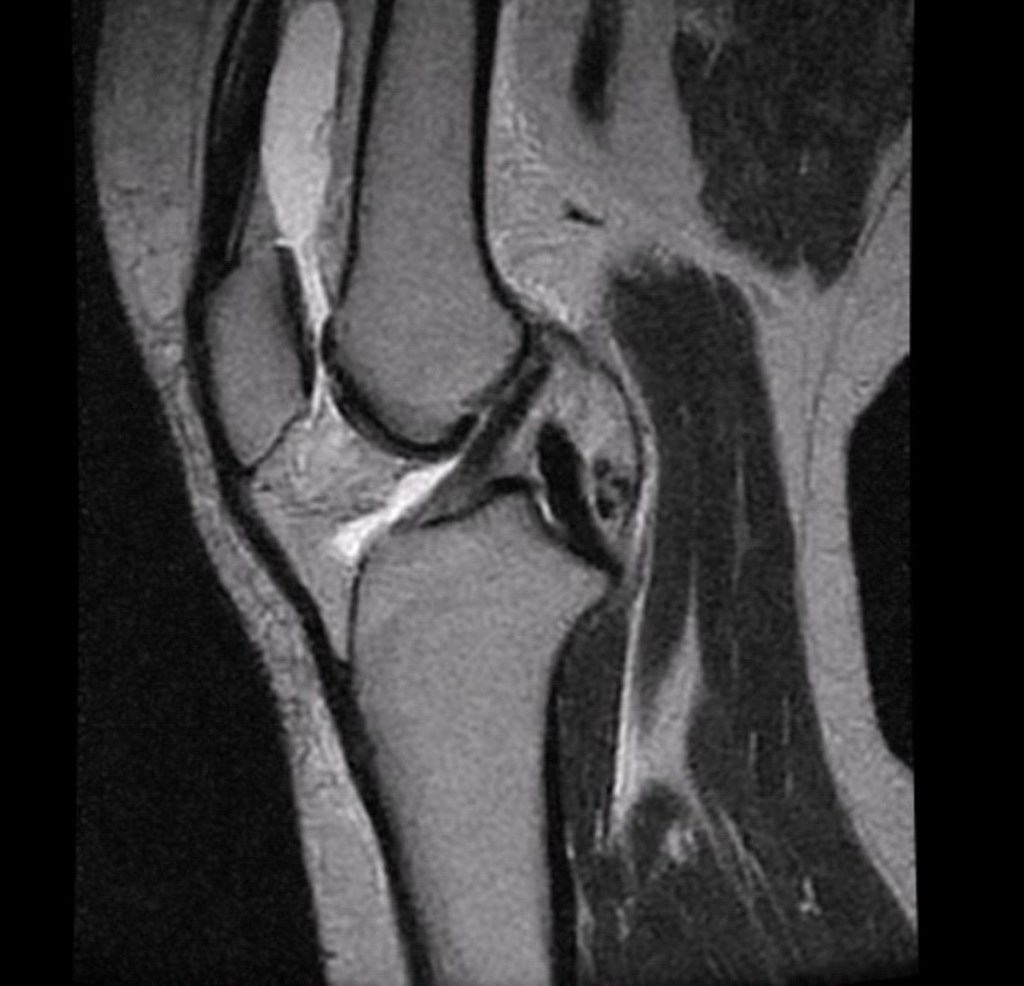

Dr Ryan Kohler performs his own specialist diagnostic ultrasound with the latest high-end I700 Canon Ultrasound machine at no extra cost during your initial consult.

There is no need to have an ultrasound elsewhere before your first consultation. This enables rapid diagnosis of the injury.